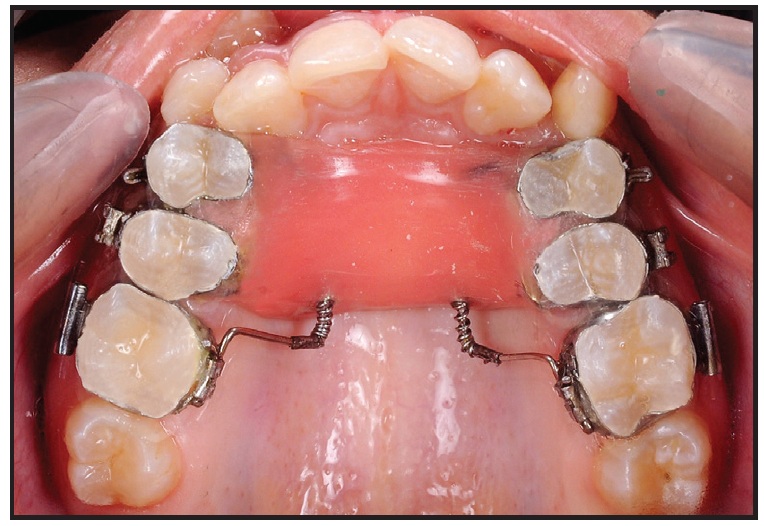

Upon completion of Phase I, a Nance palatal button was placed to maintain the correction. Phase II was then initiated by bonding the upper arch except for the canines and inserting an .014" nickel titanium wire. The second premolars were distalized first, followed by the first premolars to prevent anchorage loss. Once enough space had been gained, the canines were bonded and actively pulled into the arch with a piggyback .014" nickel titanium wire. After archwires had progressed up to .019" × .025" stainless steel, +7° torque brackets were bonded to the upper canines to move their roots into the center of the buccal and palatal cortical plates. Clinical observation of similar cases has shown that buccally placed upper canines require positive torque because of their root positions. The upper arch was leveled and aligned in 13 months of Phase II treatment (Fig. 5, Table 1). After appliance removal, upper and lower 3-3 fixed lingual wires were bonded and upper and lower Hawley retainers were delivered.

Fig. 5 Case 1. Patient after 19 months of treatment.